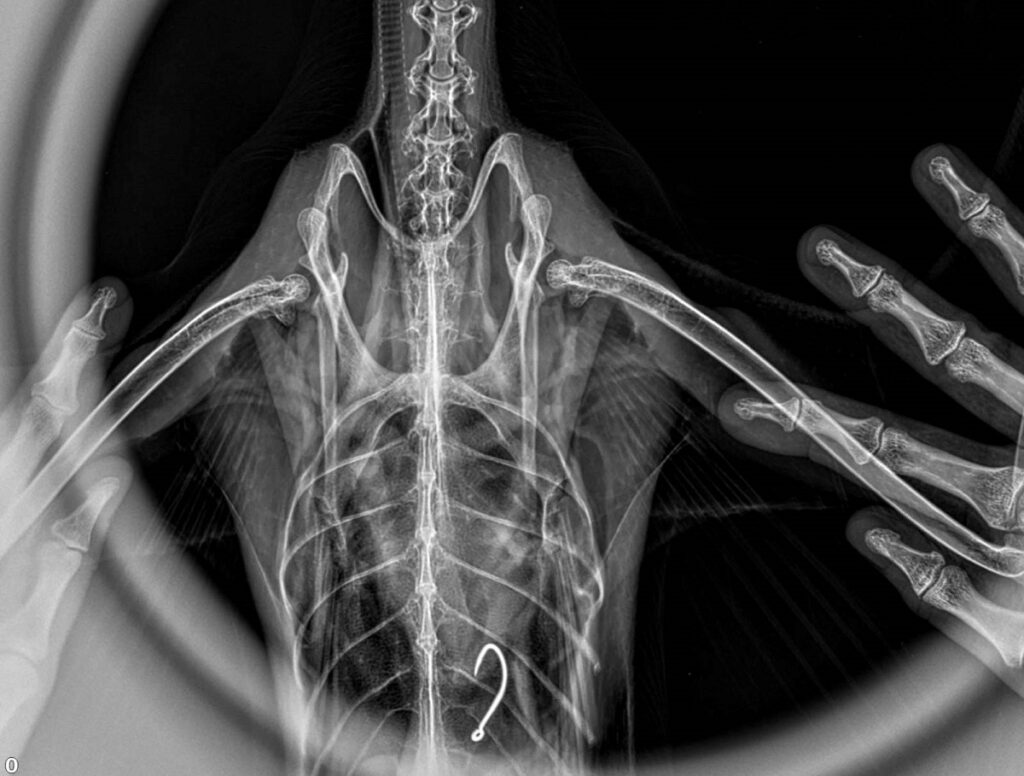

Ветеринари дослідили, що гачок залишився у шлунку баклана.

Фахівці кажуть, що інородне тіло в організмі птаха може вести себе по-різному: може капсулюватися, а частина, навіть, може розсмоктатися.